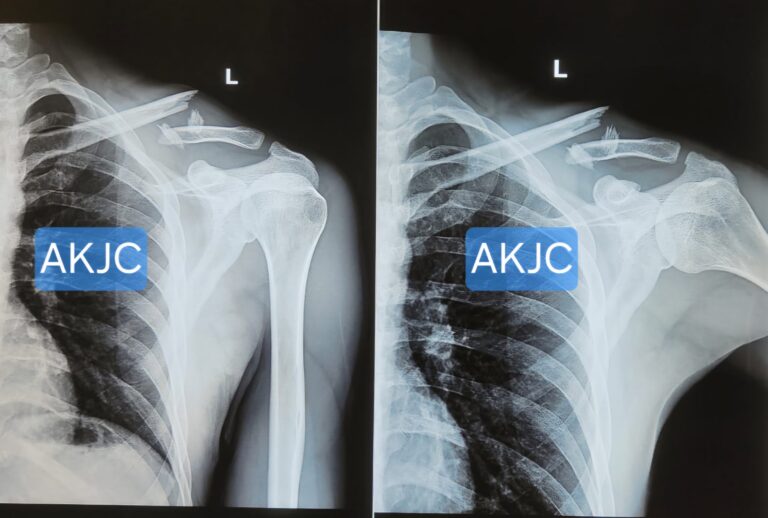

This is a real pre-operative X-ray of a displaced middle shaft clavicle fracture seen at our clinic in Indore.

This is the most common type, accounting for around 70–80% of cases.The break occurs in the central portion of the bone, which is naturally thinner and more exposed to injury.

Middle shaft fractures may be:

- Undisplaced – Bone fragments remain aligned

- Displaced – Bone ends shift out of position

- Comminuted – Bone breaks into multiple fragments

While many undisplaced fractures heal well with sling support and rest, significantly displaced fractures may require surgical fixation for proper alignment and faster functional recovery.